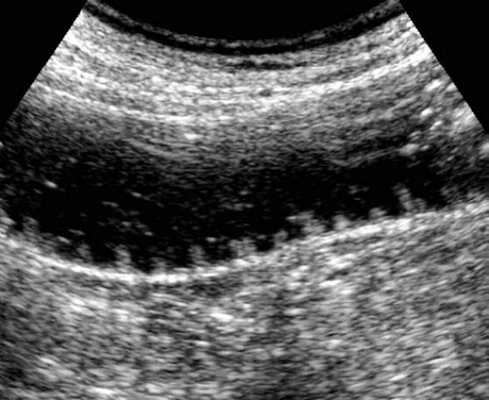

УЗД признаки тонкокишечной непроходимости

Основные УЗ-признаки при непроходмости- это визуализация расширенных петель тонкой кишки, сниженная перистальтика, свободная жидкость между петлями (танга) и в брюшной полости. Также УЗИ иногда позволяет обнаружить причину обструкции, например, опухоль, утолщение стенок терминального сегмента подвздошной кишки при болезни Крона и т.д. УЗИ может решить диагностическую дилемму при неоднозначных рентгенологических признаках на обзорной рентгенограмме брюшной полости. Лимит метода заключается в низкой специфичности при оценки состояния брыжейки, а также зависимость качества диагностики от конституции пациента и опыта оператора.

примеры сонограмм с расширенными петлями тонкой кишки

УЗИ позволяет прекрасно лоцировать свободную жидкость в брюшной полости